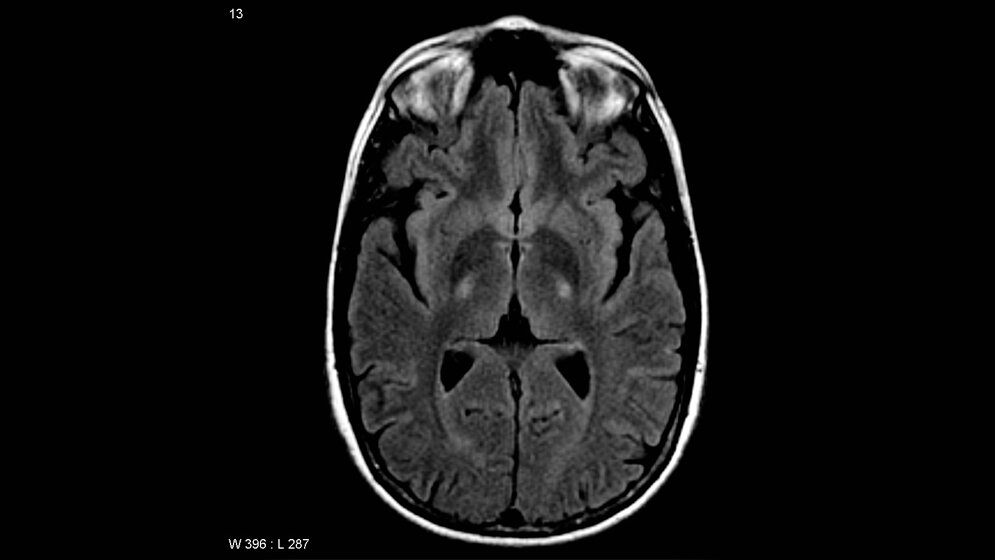

ALS ist eine komplexe und derzeit unheilbare neurodegenerative Erkrankung, die zum Untergang der motorischen Nervenzellen und somit zu stetig fortschreitenden Lähmungen führt. Die relativ seltene Krankheit – etwa drei von 100.000 Personen sind jährlich neu betroffen – wurde durch prominente Patienten wie den Physikprofessor Stephen Hawking und die „Ice Bucket Challenge“ im Sommer 2014 bekannter. In der Regel führt ALS innerhalb von drei bis fünf Jahren nach Krankheitsbeginn zum Tod. Unterschieden wird die sporadische Variante von der erblich bedingten („familiären“) Form, die nur etwa 10 Prozent der Erkrankungen ausmacht. In beiden Fällen ist die Krankheitsentstehung noch nicht genau verstanden. Zwar konnten Wissenschaftler dank jüngster Fortschritte in der DNA-Sequenzierungstechnologie mehrere Gene identifizieren, deren Mutation eine Prädisposition für ALS darstellt. Diese Mutationen erklären jedoch lediglich die Ursache von weniger als 25 Prozent aller Krankheitsfälle.

Das KIF5A-Gen ist der Bauplan für ein Protein, das am Transport von Substanzen im Axon einer Nervenzelle beteiligt ist. Die Studienergebnisse unterstreichen also die Bedeutung von intrazellulären Transportprozessen bei der ALS-Krankheitsentstehung. Zudem sind weitere neurologische Erkrankungen mit unterschiedlichen Veränderungen im KIF5A-Gen assoziiert (hereditäre spastische Paraplegie, Charcot-Marie-Tooth-Krankheit Typ 2, Neonatal intractable myoclonus). In Zukunft könnten die nun veröffentlichten Erkenntnisse zu neuen molekularen Therapieansätzen beitragen.